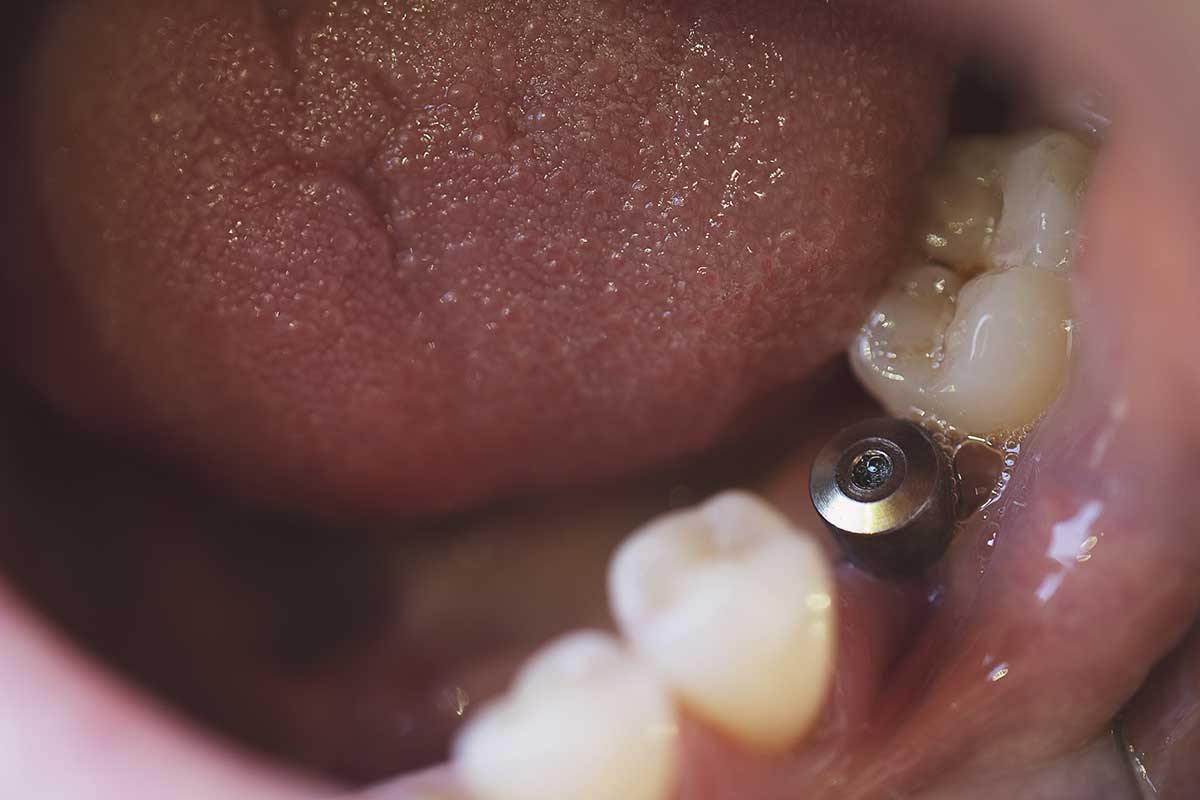

Dental implants are a type of permanent structure added into the opening created by the lost tooth. These screws, which are titanium cylinders, create an anchor into the jawbone where the tooth is missing. After this is placed and the bone grows to secure it, a new dental crown is added to the top. A crown looks like a natural tooth. It can also be sized, colored, and designed to look like your other teeth.

Implants can be used to replace one or more teeth. Sometimes, a single tooth implant can be placed to support up to three crowns. These devices can last for decades and create a long-term solution for those who have missing teeth.